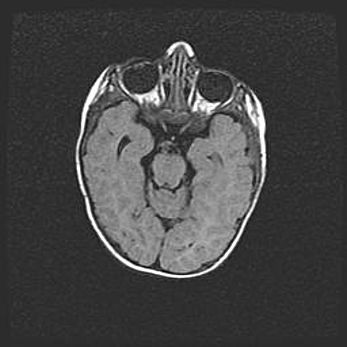

Неполная лизэнцефалия (пахигирия). Открытая гидроцефалия.

Возраст: 17 дней

Вес: 3110 г

Пол: мужской

Окружность головы: 33,5 см

Срок гестации: 35-36 недель

Лизэнцефалия—недоразвитие корковой пластинки и мозговых извилин в результате нарушения миграции нейронов коры. Поверхность мозговых полушарий гладкая. Микроскопически выявляется отсутствие нормальных слоев коры и скопление групп нейронов в подкорковом белом веществе.

Пахигирия—уменьшение числа вторичных извилин. В пораженном полушарии нервные клетки образуют толстый недифференцированный слой с неправильно расположенными нервными волокнами и группами гетеротопных клеток. Нервные клетки незрелые. Белое вещество истончено. При этом нередко аномально развит корково-спинномозговой путь.